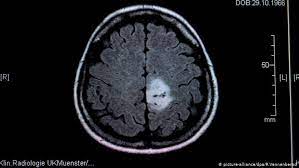

How Can You Tell If A Baby Has A Brain Tumor - Brain Tumors In Children Symptoms Diagnosis And Treatment / The signs and symptoms of a brain tumor vary greatly and depend on the brain tumor's size, location and rate of growth.

How Can You Tell If A Baby Has A Brain Tumor - Brain Tumors In Children Symptoms Diagnosis And Treatment / The signs and symptoms of a brain tumor vary greatly and depend on the brain tumor's size, location and rate of growth.. That's 13 children a day, 91 children a week and 4,760. Doctors sometimes discover these growths by happenstance: The types of brain tumors are based on the cell type and location in the brain. General signs and symptoms caused by brain tumors may include: Headaches are common with brain tumors, but studies show that it is actually a seizure or other neurological symptom that usually appears first.